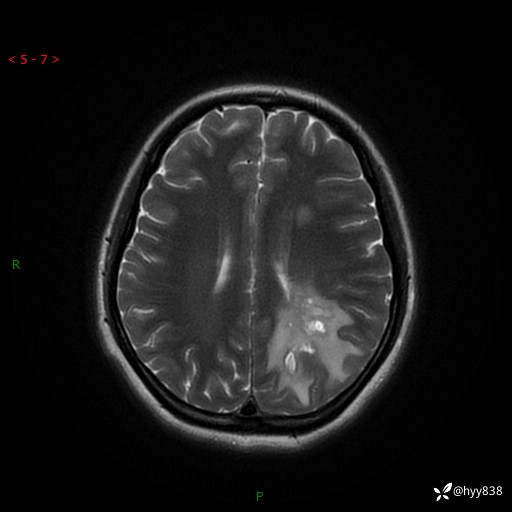

颅脑MRI平扫+增强